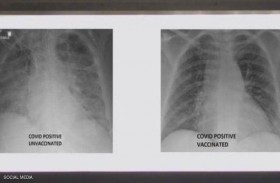

ملقح وغير ملقح...صور الأشعة تكشف أثر كورونا على الرئتين

نشر الطبيب العربي في الولايات المتحدة، غسان كمال، صورة تظهر الفرق بين رئتي شخص جرى تطعيمه ضد فيروس كورونا ورئتي شخص آخر لم يتلق التطعيم، مشيرا إلى أن الاثنين أصيبا بفيروس كورونا. وأظهرت ... إقرأ المزيد